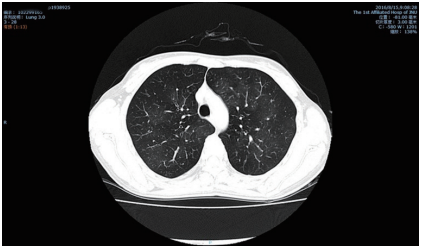

抗SSA(−),抗SSB(−),HLA-B27阴性。胸部CT:双肺见多个条片状淡薄高密模糊影及散在磨玻璃

影,双上肺尖段见少量条索影,考虑间质性肺炎并肺气肿(图4);最终诊断为“ Stevens-Johnson综

图4 双肺见多个条片状淡薄高密模糊影及散在磨玻璃影

Figure 4 Multiple band-shaped thin and high-density shadow

and scattered ground glass in bilateral lungs